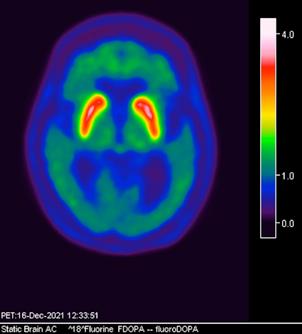

CASO CLÍNICO

Actualmente, el diagnóstico del Parkinson se basa principalmente en métodos convencionales que incluyen: -Presencia de 2 de los 3 síntomas principales, con ausencia

axial fusionada de PET-RM 3T con

con disminución de la captación del radiotrazador a nivel de ambos putámenes en la región posterior y media de predominio derecho así como disminución en el caudado ipsilateral.

2. Reconstrucción tridimensional avanzada de imagen híbrida PET-RM 3T con 6-[18F]FDOPA observando disminución de la captación del radiotrazador a nivel de ambos putámenes en la región posterior y media así como en el núcleo caudado derecho.

Figura 3. Reconstrucción mediante imagen molecular de imagen híbrida PET-RM 3T con 6-[18F] FDOPA observando disminución de la captación del radiotrazador a nivel de ambos putámenes en la región posterior, media y anterior así como en ambos núcleos ca dados de predominio derecho.

Figura 4. Reconstrucción mediante imagen molecular de imagen híbrida PET-RM 3T con 6-[18F]FDOPA observando captación adecuada y conservada del radiotrazador en el cuerpo estriado (ambos putámenes y núcleos caudados) en un paciente negativo para enfermedad de parkinson.

En cuanto al campo de los estudios de imagen convencional y de laboratorio no existe alguna prueba que pueda confirmar la enfermedad. Sin embargo, las imágenes de diagnóstico por métodos de imagen molecular del tipo no invasivas, como la tomografía por emisión de positrones (PET) en conjunto con un resonador de 3 tesla (RM 3T), pueden respaldar el diagnóstico de un médico, actualmente éste método tiene una sensibilidad diagnóstica de 95.4%, especificidad 100%, valor predictivo positivo del 100% y valor predictivo negativo del 87.5%. (5,6)

La enfermedad de parkinson es una enfermedad neurodegenerativa con afectación principalmente motora (temblor, rigidez y acinesia) de sospecha y diagnóstico clínico, ante la limitación de los estudios de laboratorio y métodos de imagen convencional para el diagnóstico toman gran relevancia las técnicas de imagen molecular no invasivas como el PET-RM y PET-CT con 6-[18F]FDOPA que cuentan con gran sensibilidad y especificidad para respaldar o descartar el diagnóstico médico ante la sospecha de la enfermedad de parkinson y algunas otras enfermedades del trastorno del movimiento.